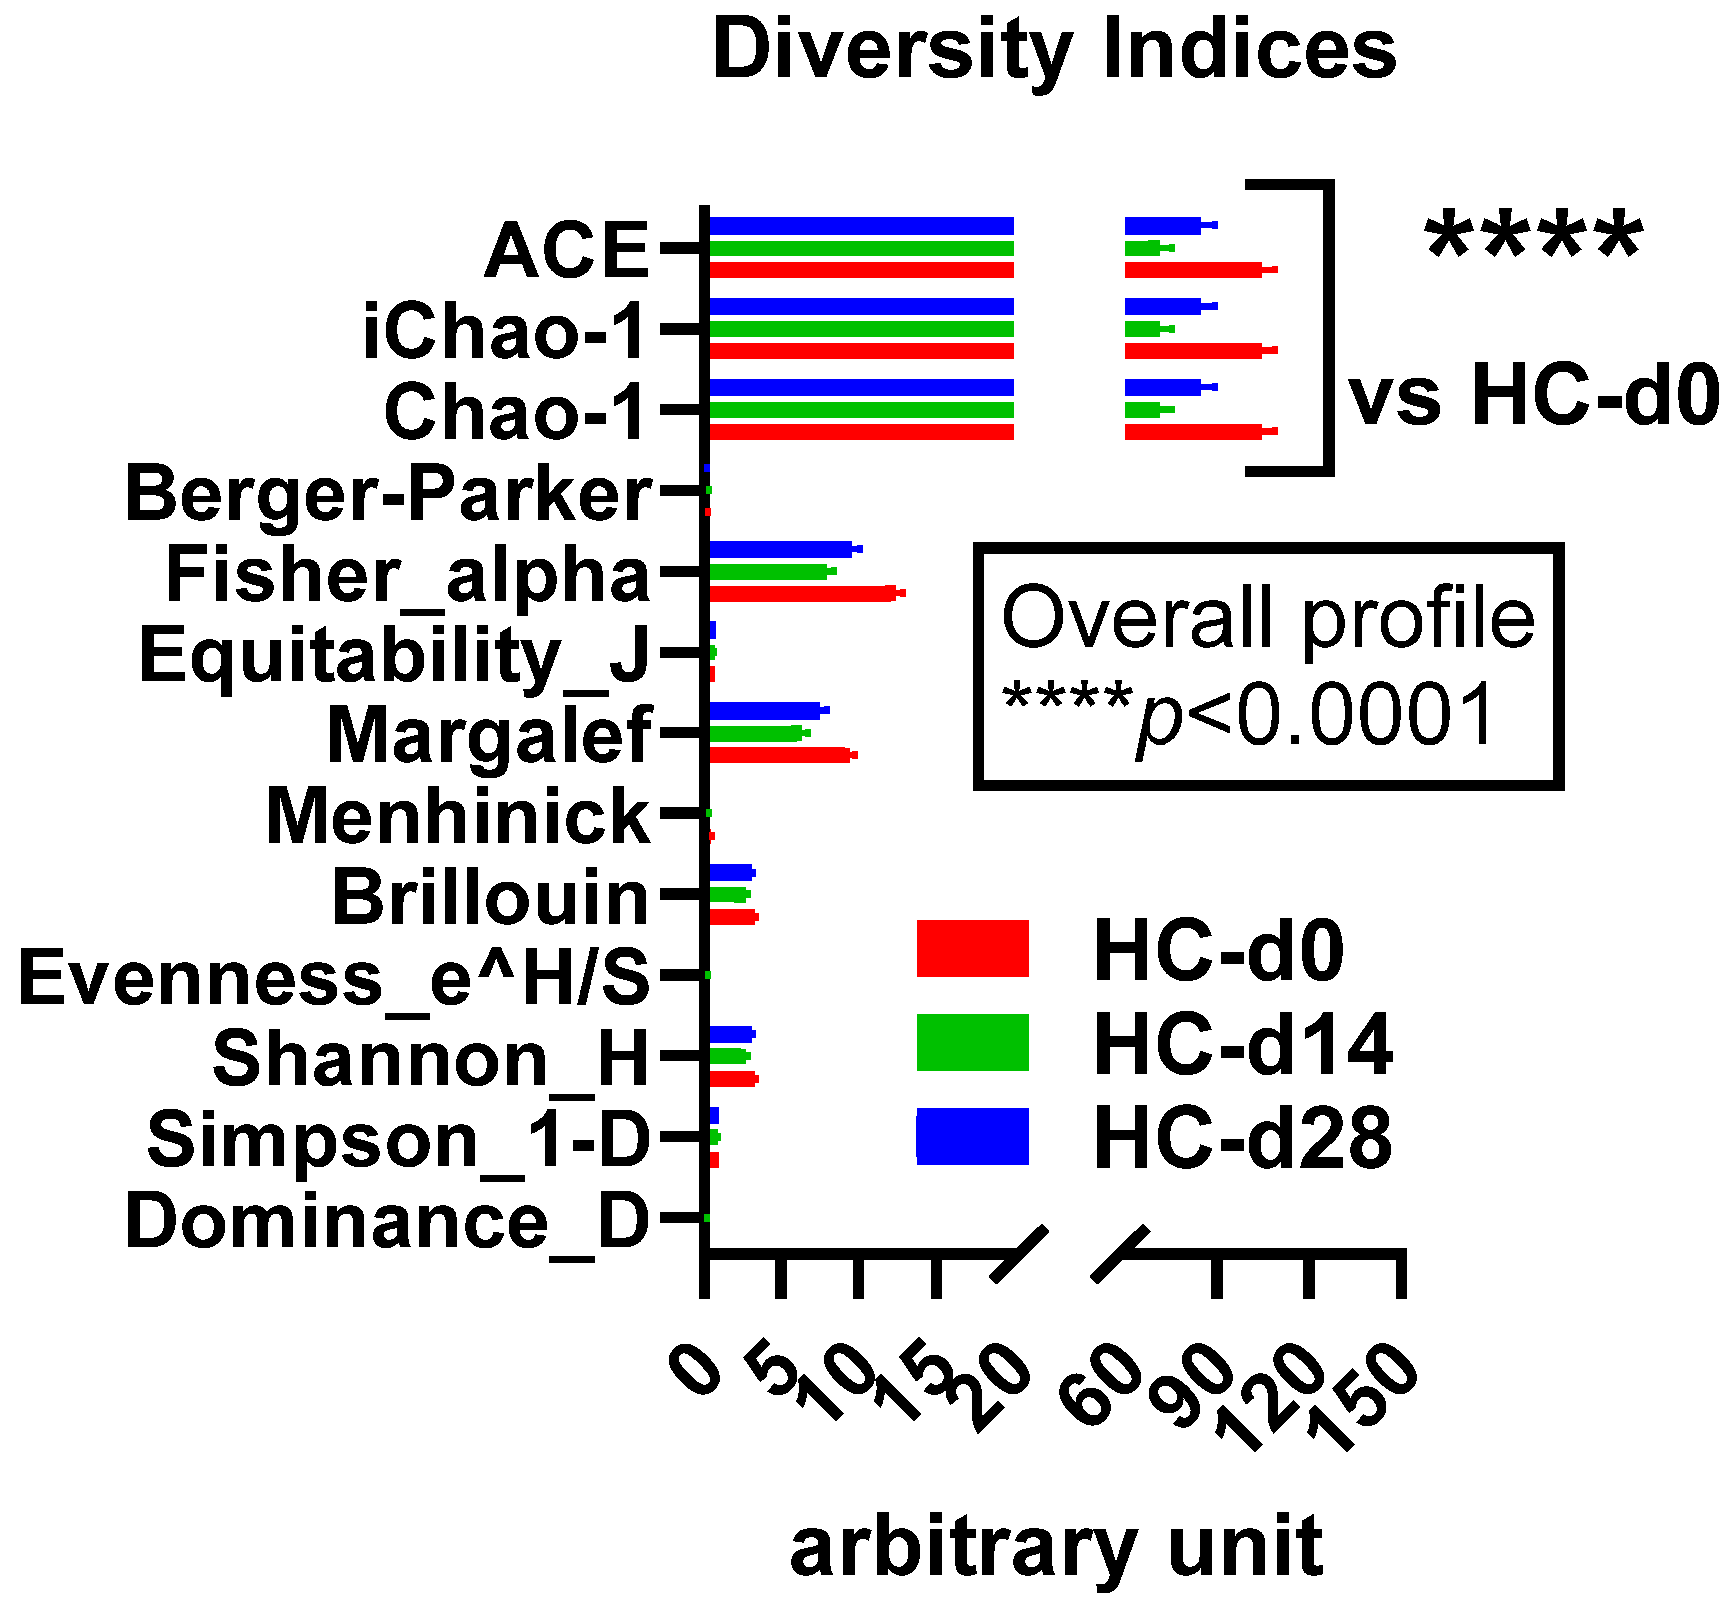

3.3.1. Alpha Diversity

3.3.2. Beta Diversity